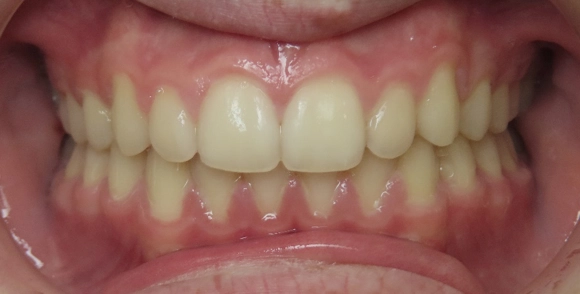

Deep Bite Before and After

After

Deep bite treated with braces